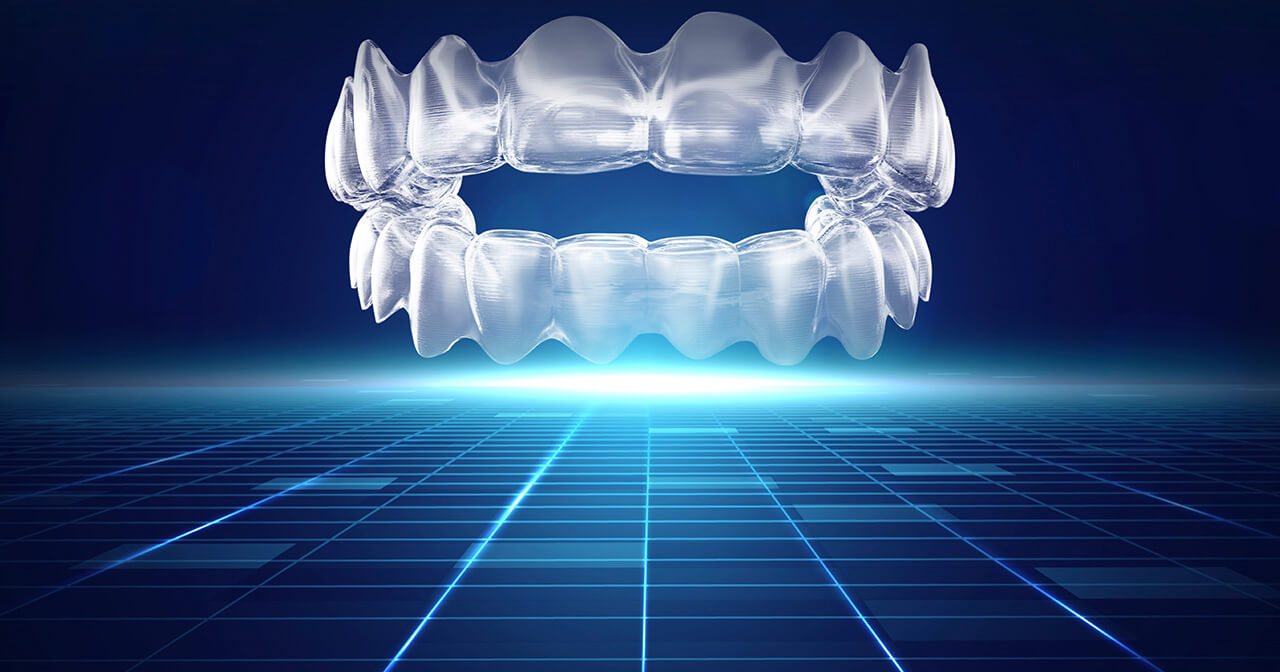

Artificial Intelligence (AI) driven customised orthodontics is the future

BOSS News, Dr Katyal’s PublicationsAI can help deliver orthodontic treatments predictably and in patient-friendly ways. Latest technologies combined with customised aligner-based orthodontics can help set your practice apart and improve your case acceptance.

The Future of Orthodontics is no longer driven by appliances but by Artificial Intelligence (AI). AI is now available for orthodontic diagnosis, treatment planning and treatment monitoring. It is the automated extension of tele-dentistry which has been used in orthodontics since the 1990s (Estai et al 2018). AI technology use big data sets and computer programmers to teach it to recognise whether a condition is true or false.

Do orthodontic treatments finish faster with AI? Treatment times depend on a number of factors and all virtual treatment monitoring detects is progress, breakages and aligner fit (tracking) against the proposed treatment plan. If all other factors are favourable, we should see a reduction in aligner unseats and be able to assess breakages quickly. Our pilot data shows aligner patients are more compliant with prescribed wear time when AI technologies are used – the compliance rose from 50% to 90%. This shows that we should be f